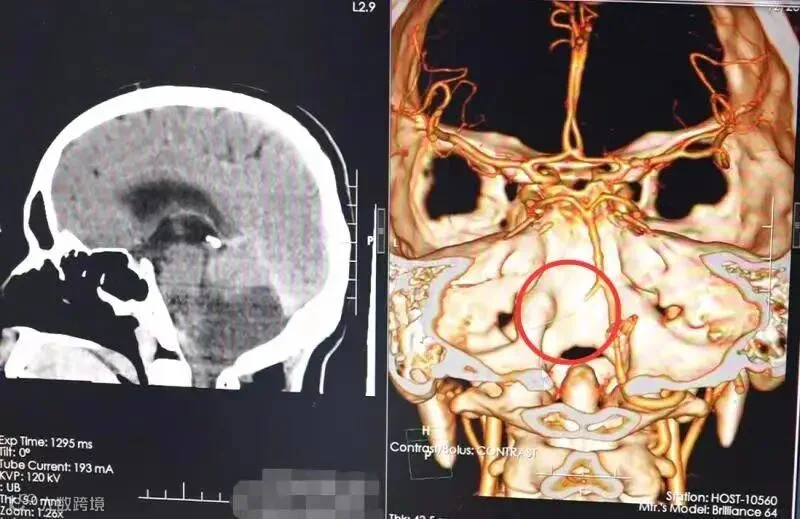

在当地医院,钟先生被诊断为左侧小脑梗死合并有脑积水,但给予脱水等对症治疗后,症状并没有好转。

该院接诊的神经外九科主任穆林森仔细观察患者的体征,结合外院的影像检查资料,认为小脑梗死诊断明确。

完善相关检查后,穆林森发现患者有小脑扁桃体下疝。

检查提示,钟先生脑梗死。

为避免脑疝进一步加重导致呼吸心跳骤停等严重后果,10月30日,穆林森团队为患者急诊实施了后颅窝去骨瓣减压术和右侧脑室外引流术,顺利切除了部分梗死的小脑组织。术后给予营养神经、补液等对症治疗后,钟先生于近日顺利出院。